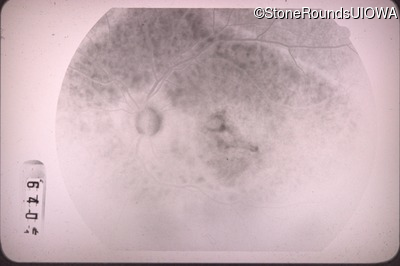

Case Level Images

Diagnosis & molecular findings

Disease Gene Allele 1 variant(s) Allele 2 variant(s) Inheritance mode

Best Disease BEST1 Tyr227Asn TAC>AAC   AD